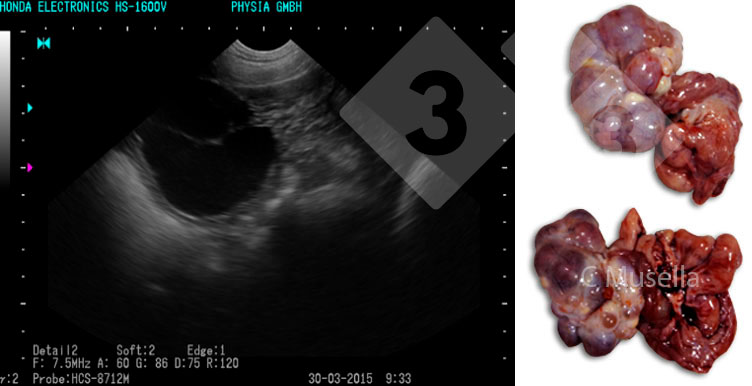

La diagnosi di cisti ovariche singole o multiple è relativamente semplice, sebbene l'identificazione completa del tipo di cisti mediante ecografia non sia sempre certa.

Per quanto riguarda le strutture uterine, la presenza di liquido, non attribuibile a gravidanza, seme o calore, è da considerarsi patologica e indicativa di un'infiammazione essudativa nell'utero. L'osservazione ecografica dell'essudato è possibile solo in caso di infiammazione acuta.